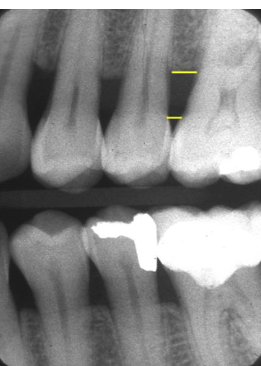

alveolar bone level runs ___ to the levels of the 2 CEJs

parallel

healthy distance from CEJ → alveolar bone

2-3 mm

3 types of perio pockets

normal: apical termination of junctional epithelium is at CEJ

supraboney: proliferating pocket epithelium + remnant of junction epithelium persists

infraboney: extends beyond alveolar crest